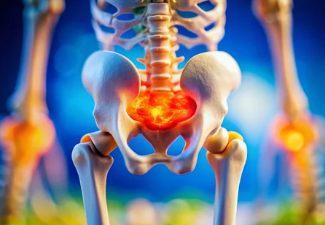

✅ (2) 경미한 충격에도 골절 위험 증가

✔ 심한 경우 낙상, 미끄러짐, 가벼운 충격에도 뼈가 골절될 가능성 증가

✔ 손목, 척추, 고관절 부위에서 골절이 잘 발생함